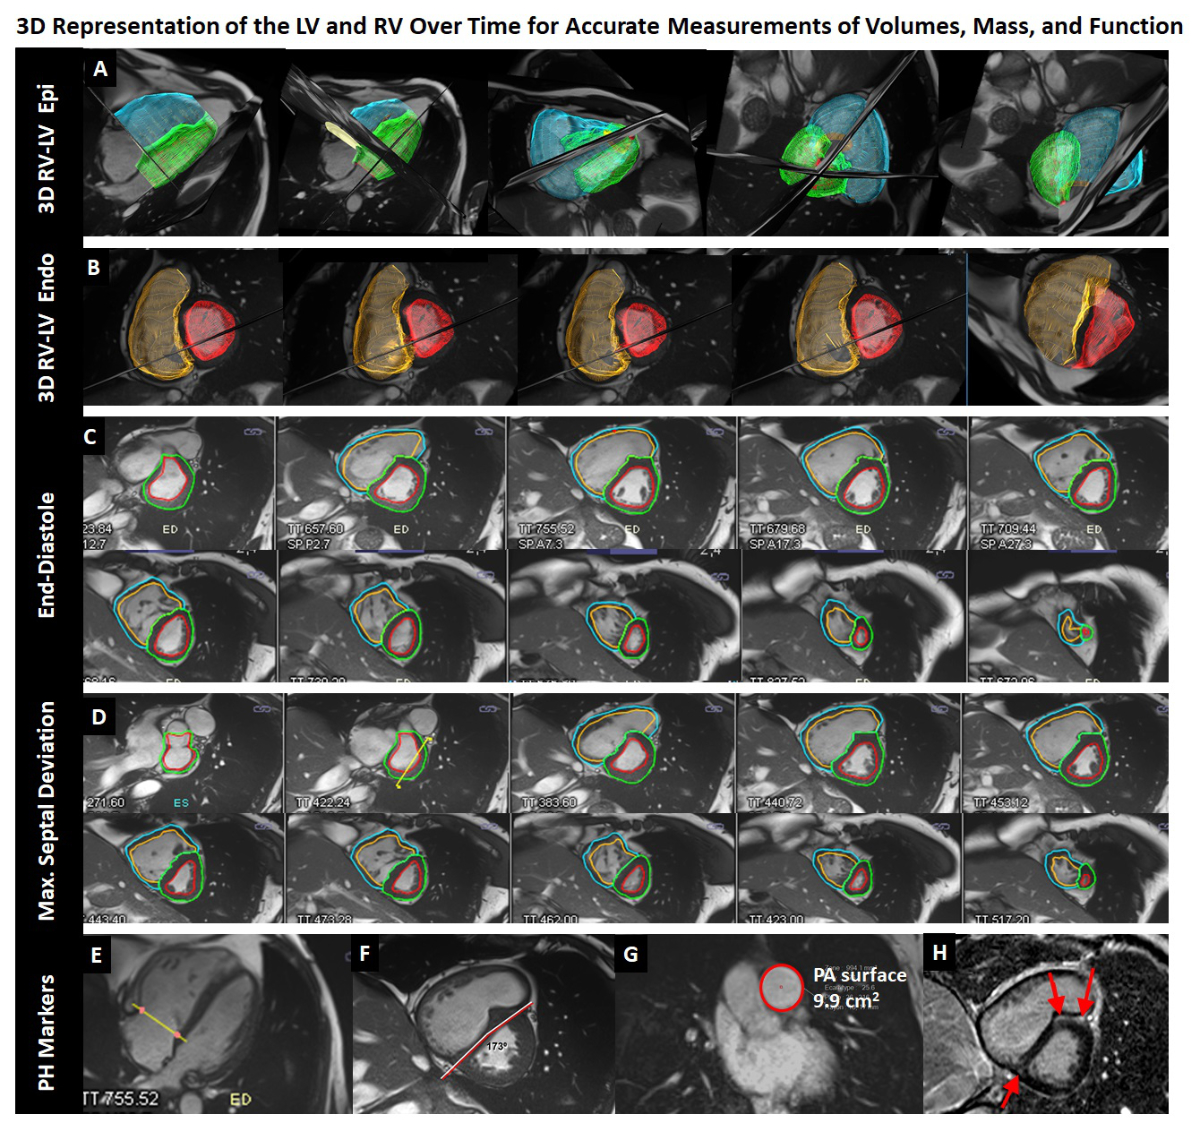

Figure 2 Example of a 45-year old man with idiopathic PAH suffering from dyspnoea on exertion.

The cardiac MR (CMR) examination consists of cine short-axis (C, D) and long-axis acquisitions (E) covering the entire right and left ventricles (RV, LV). Post-processing allows reconstruction of three-dimensional representations of the RV and LV (A, B) for accurate quantification of end-diastolic and end-systolic volumes, stroke volumes, and RV and LV myocardial mass. In this patient, the RV is dilated and hypertrophied (239 ml, 126 ml/m2 at end-diastole, 83 g, 44 g/m2) and the ejection fraction is severely reduced to 14%. A typical D-shape deformation of the septum is observed at end-systole / early diastole. The interventricular septal angle was 173⁰, the RV/LV mass ratio was 83 g/159 g, and diastolic pulmonary artery area was 9.9 cm2. According to the model developed by Johns et al. [38] these measurements translate into an approximate mean PA pressure of 44 mm Hg; a right heart catheterisation performed 16 months later yielded 42 mm Hg. These data indicate that the RV converted from a volume to a pressure pump. Accordingly, the ventricular-arterial coupling (the ratio of RV maximum end-systolic elastance over PA effective elastance) is unfavourable in this patient and estimated by the CMR examination to be 6.2 according to Sanz et al. [33]; normal values with optimal coupling are close to 1.0.

A: blue and green 3D-meshes represent RV and LV surfaces at end-diastole, respectively, B: orange and red 3D-meshes represent RV and LV endocardial surfaces at maximum septal deviation, respectively. Corresponding contours on short-axis cine images (out of a series of 25 frames per heart beat) are given in C and D, respectively. F: short-axis cine image at maximum septal deviation, G: Diastolic area of the pulmonary artery, H: short-axis late-gadolinium enhancement image demonstrating intramyocardial fibrosis (bright areas) in the anterior and posterior insertion point of the RV at the septum.